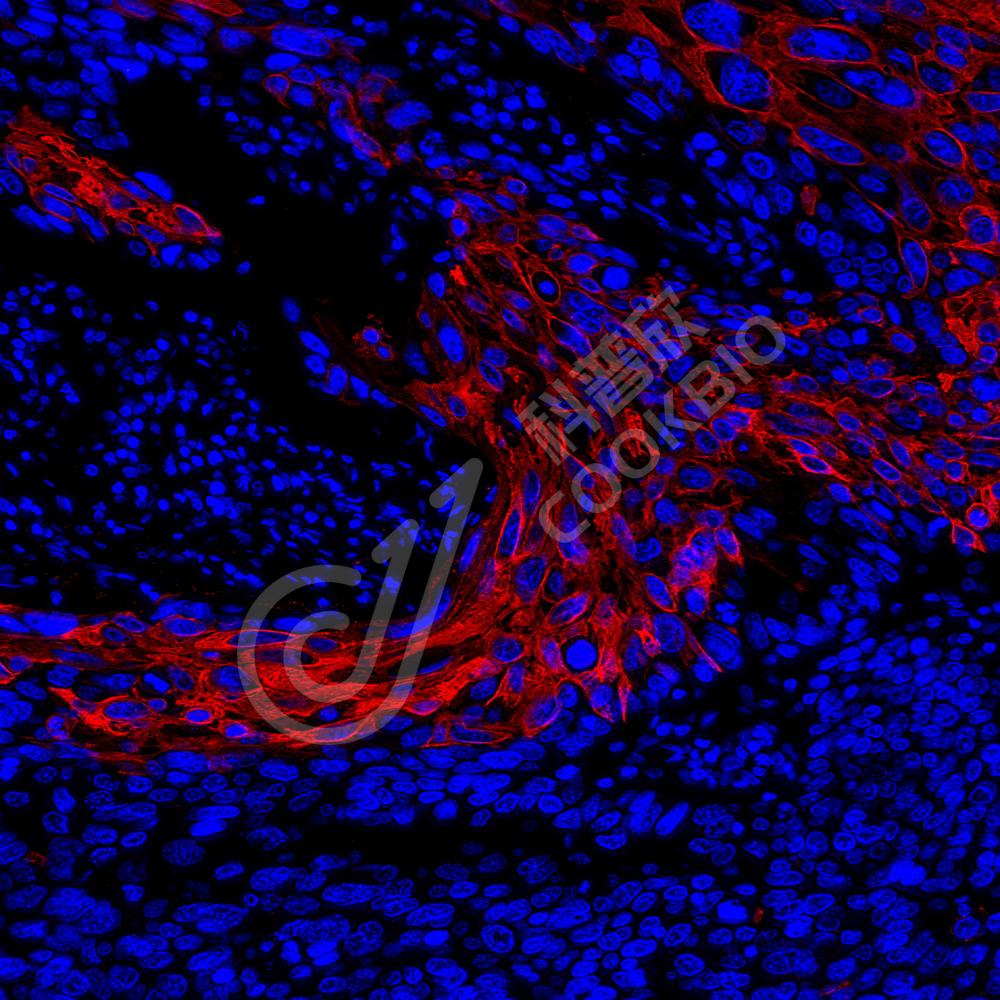

IF检测Cytokeratin 5蛋白(货号 K1333738)(红色).

样品: 人乳腺癌, 4%多聚甲醛 (货号KSG1101) 固定12-24小时.

抗原修复: Tris-EDTA抗原修复液(pH 9.0) (KSG1203), 98℃, 20分钟.

封闭: 3% BSA(货号KSGC305010)的PBS溶液, 室温孵育30分钟.

—抗: 1: 2000稀释, 4℃ 孵育过夜.

二抗: Cy3标记山羊抗兔IgG (H+L) (货号KB63909), 1: 300稀释, 室温孵育1小时.